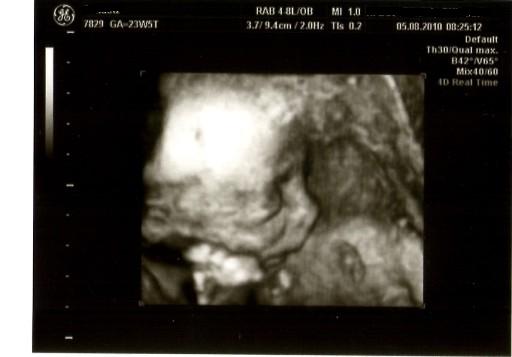

Wir hatten schonmal darüber gesprochen das Justin lieber einen Bruder hätte, aber mittlerweile freut er sich sehr auf seine Schwester vorallem nach dem letzten US als sie uns so frech die Zunge gezeigt hat das fand er total super!